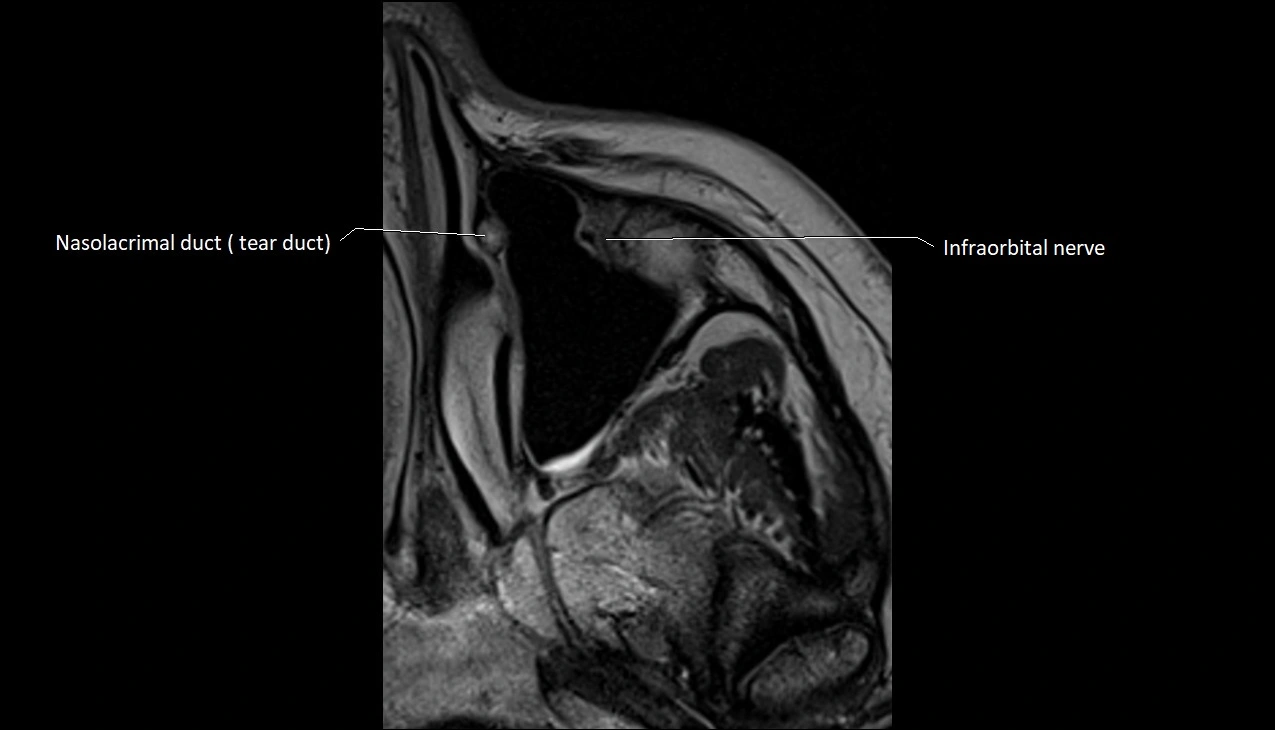

- Infraorbital nerve

- Nasolacrimal duct (Tear duct)